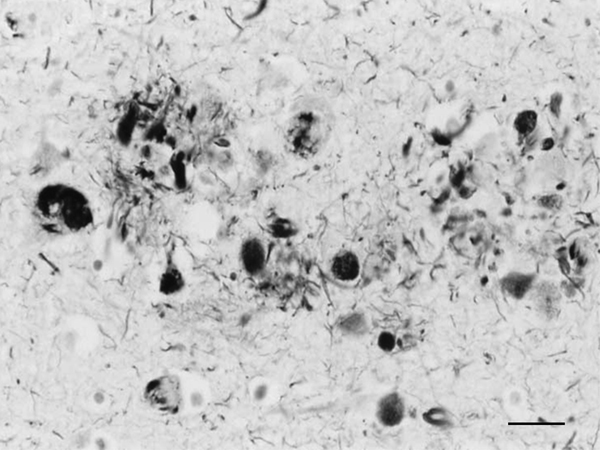

The main constituent of NFTs dystrophic neurites of SPs and neuropil threads is abnormal tau (158-173) (Figures 5, 6, and 7). A combination of all six hyper-phosphorylated brain tau isoforms (3Rtau and 4Rtau expressed in brain), generated from alternative tau splicing, is characteristic of AD tau (163, 174, 175). The amount of 3Rtau is similar to 4Rtau in the human adult brain and in AD. However, possible variations in the ratio of 3Rtau/4Rtau among cell types in the human brain have not been adequately assessed. Abnormal tau in AD includes several species resulting from hyper-phosphorylation at different sites, acetylation, glycosylation, altered confor mation, truncation at glutamic acid 391 and at aspartic acid 421 (mediated by caspase 3), oligomerization, and β-sheet-rich fibril aggregation, among others (171-173, 176-196). The site of tau phosphorylation and other post-translational modifications in tau have commonalities and differences among tauopathies (197, 198). Tau inclusions in glial cells are not found in AD, unless accompanied by other tau co-morbidities including aging-related tau astrogliopathy (ARTAG) and argyrophilic grain disease (AGD) which are 4Rtau-only tauopathies.